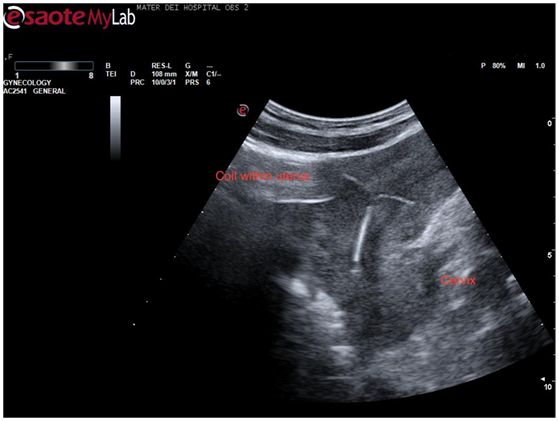

Returning to the sagittal view of the uterus the entire uterus was visualized and on sliding the probe across the uterus in this plane, the intrauterine contraceptive device came clearly into view (Figure 3). This was quite a dramatic view as the whole intrauterine device was seen to be placed inside the body of the uterus. The patient became visibly anxious at this stage so care was taken to reassure her and explain the findings thus far. By sliding the probe again an image was obtained showing both the coil and the gestation sac in the same view which confirmed that this was a case of pregnancy with a coil in situ (Figure 4).

Figure 3 Sagittal view of the uterus with coil seen in its entire length within endometrial cavity.

Figure 4 Sagittal view of the uterus showing both coil and gestation sac.